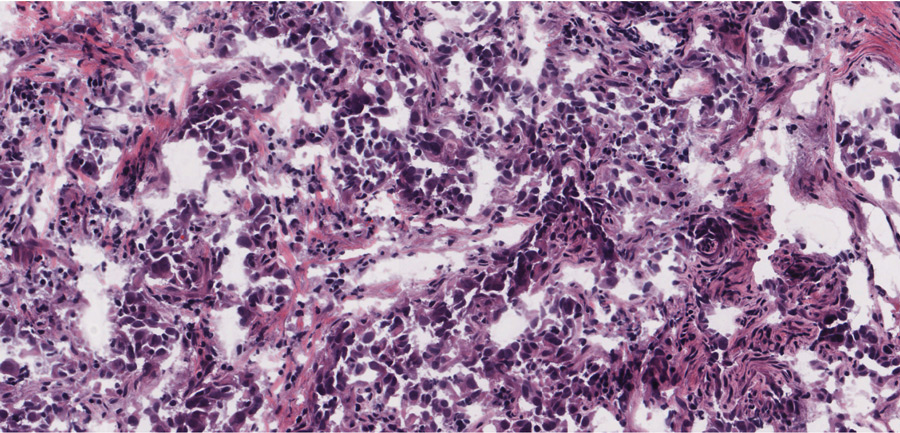

武博士通过实验多条细胞线 发现突变对selpercatinib和pralsetiib都产生抗药性细胞文化用药集中度提高处理,最终导致进化抗药性Subbiah博士一直在治疗并跟踪参加这些小说RET-ibitor临床试验的RET阳性癌症患者多数病人响应理疗,取肿瘤缩影扫描提高生活质量大约两年后 药厂停止工作这是因为癌症开发机制使药物失效被称为进化抗药Mooers博士和Wu博士在结构中看到的抗机制也见诸肿瘤,肿瘤成为抗治药在某些情况下,启动下游RET目标完全绕过RET在其他例子中,有直接配药变异如前所述,这些抑制器不绑住RET门区,因此能够克服守门人变换的阻抗非看门突变似乎应对病人和细胞文化所见的抵抗负责。

反变异细胞培养顺序排列,无细胞抗药性患者脱氧核糖核酸排序变异被确定为溶剂前端、链形和ret2线域以上所有领域都与Selpercatinib或pralseti对这两种药最强抗药性表现为溶剂前端区810残留物替代物,这意味着RET加甘油810变异最小受这些药抑制,对产生获取抗药性尤其重要